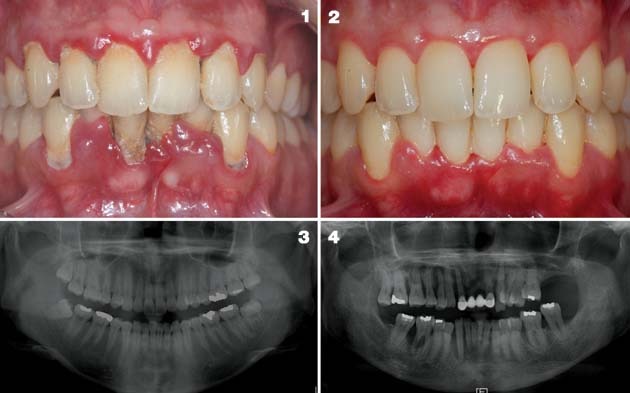

전신 염증을 줄이고 테스토스테론 회복을 위해 치주 치료는 선택이 아닌 필수! 치과 치료를 통해 잇몸 염증이 완화되면, 우리 몸은 불필요한 면역 반응에서 해방되고 호르몬 생성과 분비 시스템이 다시 안정됩니다.

이는 단순히 잇몸 상태가 나아지는 것 이상의 효과를 가져오며, 피로감 감소, 집중력 향상, 활력 회복, 심지어 기분까지 개선되는 사례가 있습니다.

이처럼 잇몸병 치료는 전신 건강, 특히 남성의 성적 자신감과 에너지를 회복하는 핵심 열쇠가 될 수 있습니다.